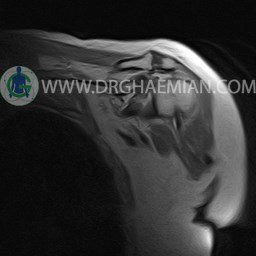

ام آر آی آتروفی عضلانی کتف بیمار

ام ار آی کتف یک روش تصویربرداری است که به وسیله آهنرباهای قدرتمند از قسمت کتف تصاویری ایجاد می کند. این نوع تصویربرداری از تشعشعات استفاده نمی کند. در این کیس آتروفی عضلانی کتف به همراه پارگی تاندون بالاخاری، بورسیت ساب دلتوئید و افیوژن مفصل دیده می شود.

– Complete tearing of supraspinatus tendon with grade 2 retraction and muscle atrophy

– AC joint hypertrophy with subacromial – subdeltoid bursitis

– Glenohumeral joint effusion

are seen.